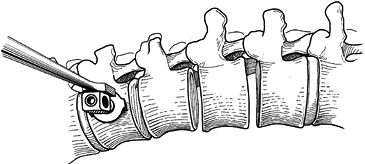

Place the end screws first from posterior

to anterior, horizontal to the frontal plane of the vertebral body and

paralleling the apex. Start the hole with an awl and continue with the

5.5 mm tap. Tap the vertebra until

P.4024

the tip just exits the far side of the cortex (Fig. 155.18).

Insert a ballpoint probe to make sure that the far side of the cortex

has been exited. Tap the first third of the hole with a 7 mm tap and

insert a 7 mm closed-top screw with washer (Fig. 155.19).

Figure 155.18.

ollowing a thorough 360° discectomy in which the posterior longitudinal

ligament is exposed, placement of the upper vertebral screw site is

begun with an awl, which is positioned at the furthest lateral waist of

the vertebral body. (Redrawn from Asher MA. Surgical

Technique for Anterior Segmental Instrumentation of Thoracolumbar and

Lumbar Scoliosis Using the Anterior Isola Spinal System. AcroMed Corp., Cleveland, OH, 1996.)

Figure 155.19. Insertion of a 7 mm closed-top screw with washer. A staple may be used if desired. (Redrawn from Asher MA. Surgical

Lumbar Scoliosis Using the Anterior Isola Spinal System. AcroMed Corp., Cleveland, OH, 1996.) -

Use a staple, and place it prior to the

insertion of the screw. Insert the screw to maximum torque. The screw

should protrude through the far cortex by at least one to two threads. -